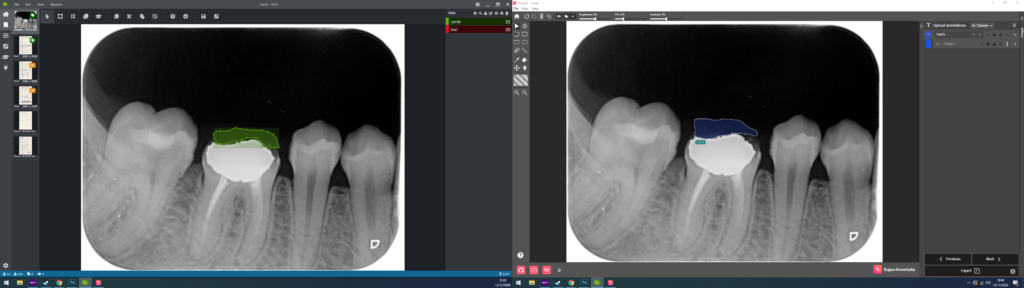

Pour chacune de vos images, vous aller devoir donc générer les masques, et par la suite les labéliser, les annoter. Via des logiciels spécialisés (VoTT, SuperAnnotate, LabelMe, etc), vous allez pouvoir segmenter vos classes au sein de vos images. Voici un Example de segmentation de Carrie sur des radiographies :